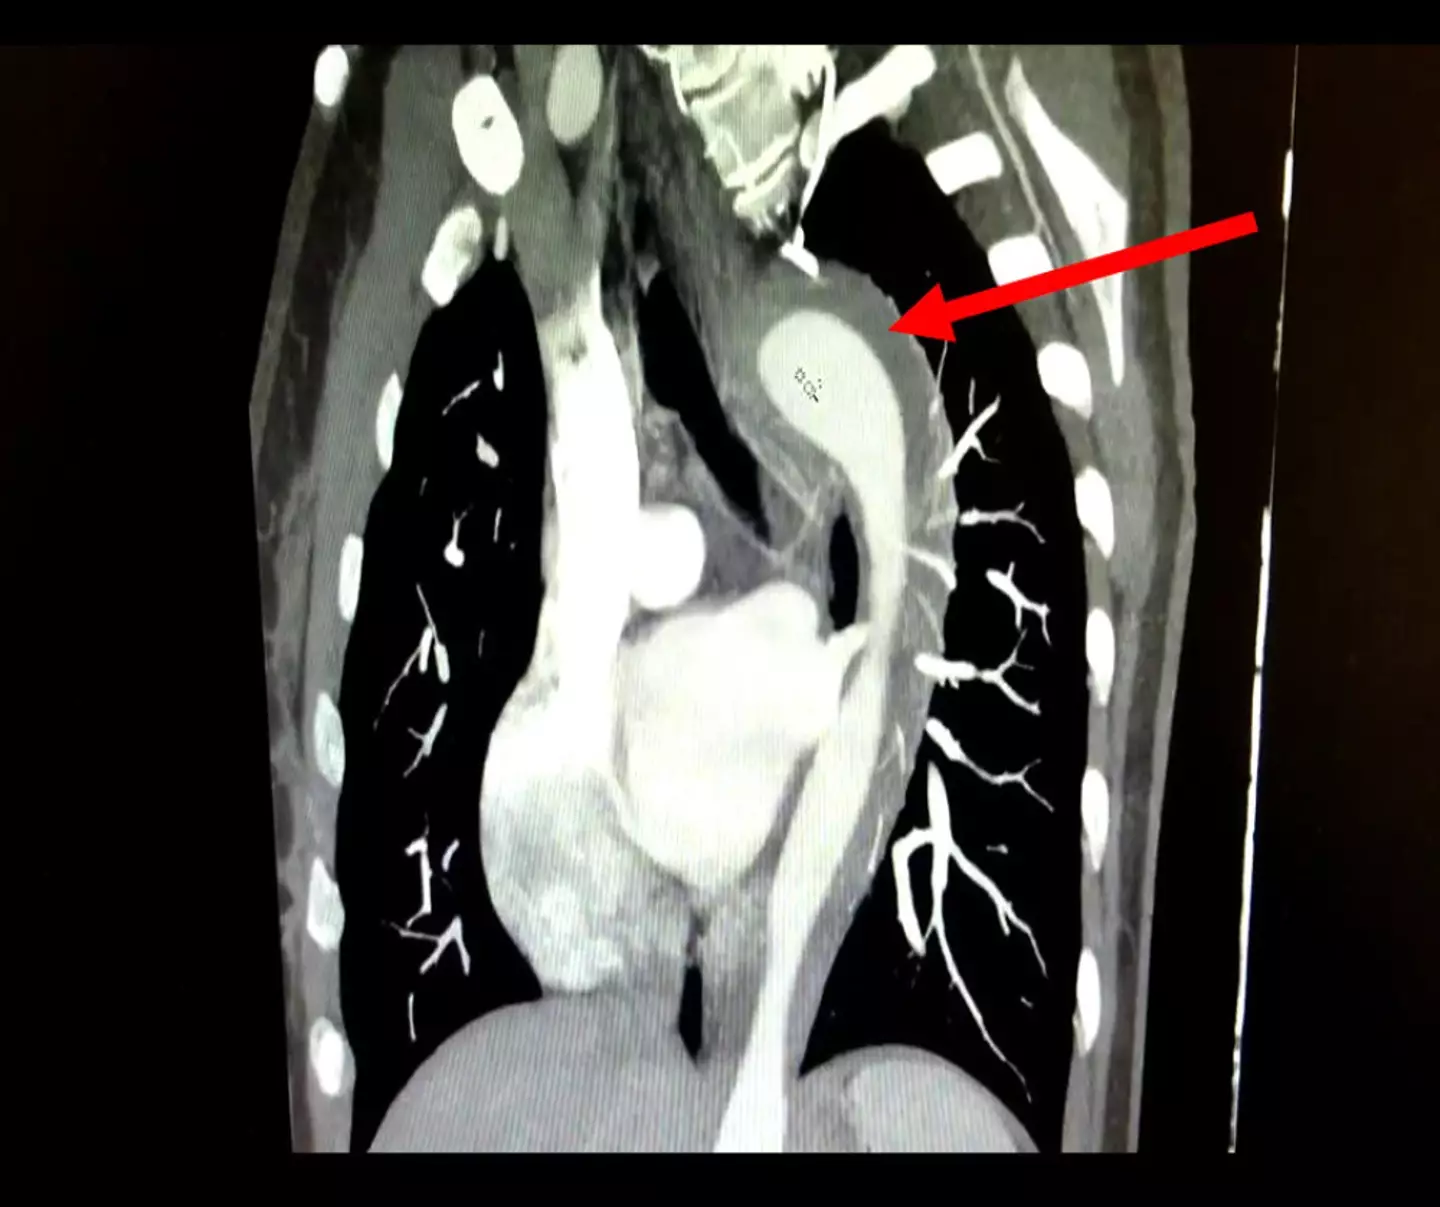

She was sent for tests and an electrocardiogram showed damage to her aorta, which doctors were able to treat without surgery.

The woman was diagnosed with acute aortic syndrome, a life-threatening condition, and it was determined that she'd suffered what doctors call an aortic intramural hematoma.

In layman's terms, that means blood is leaking through the innermost layer of the aorta and starts flowing between the inner and outer walls of the major artery.